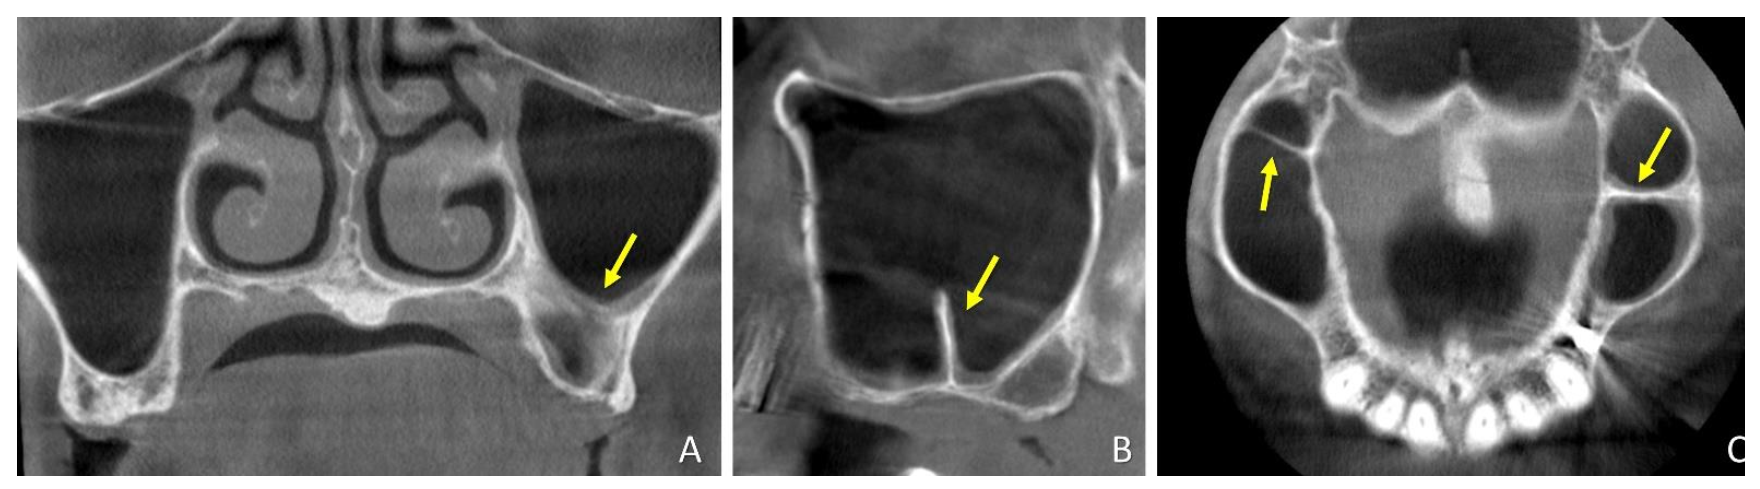

| Mucosa Area | Mesial Vertical Extension above (+) or below (−) the Z-Axis | Distal Vertical Extension above (+) or below (−) the Z-Axis | ||

|---|---|---|---|---|

| SEPTA Mean values ± SD Minimum; Maximum | T0 | 29.8 ± 30.7 b 15.8; 122.9 | - | - |

| T1w | 297.7 ± 262.0 b,c 11.8; 875.7 | 10.8 ± 9.1 c −2.8; 25.9 | 14.2 ± 10.4 2.6; 30.4 | |

| T9m | 41.2 ± 41.6 c 9.7; 157.9 | 1.7 ± 4.0 c −2.7; 8.3 | 0.7 ± 4.0 −2.8; 12.4 | |

| CONTROL Mean values ± SD Minimum; Maximum | T0 | 26.7 ± 20.0 b 11.8; 83.3 | - | - |

| T1w | 311.5 ± 205.3 b,c 21.5; 585.9 | 14.1 ± 10.8 c −5.7; 30.0 | 12.8 ± 11.1 −7.0; 36.0 | |

| T9m | 82.4 ± 144.8 c 14.2; 575.9 | 2.8 ± 6.9 c −5.9; 18.4 | 2.2 ± 6.1 −7.5; 19.0 |